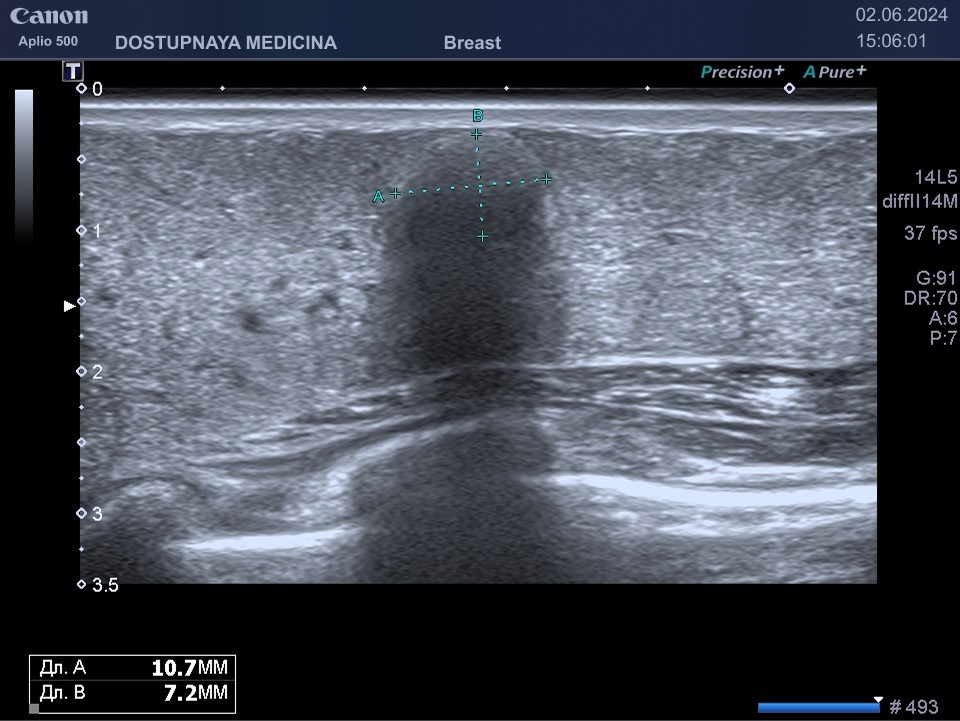

Фиброаденома молочной железы – это достаточно часто выявляемая опухоль во время ультразвукового исследования, состоящая из железистой ткани с довольно выраженной соединительнотканной капсулой.

Следует проводить дифференциальную диагностику фиброаденомы с раком молочной железы, с кистой и с цистаденопапилломой. Поэтому важно повторить ультразвуковое исследование через 3 месяца, а затем при отсутствии тенденции к росту опухоли необходим УЗИ контроль через 6 месяцев.